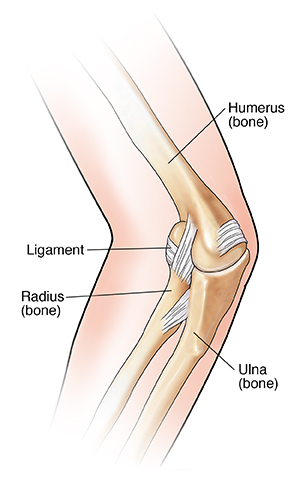

The elbow is a joint made up of three bones held in place by strong bands of tissue (ligaments). One ligament is looser in young children than in adults. As a result, soft tissue may become trapped between the bones in a child's elbow joint. The medical name for this injury is radial head subluxation. It often happens when a child is lifted or pulled by one arm, and the elbow partly dislocates.

| Radial head subluxation occurs when a ligament in the elbow becomes trapped beween the head of the radius and the humerus. |